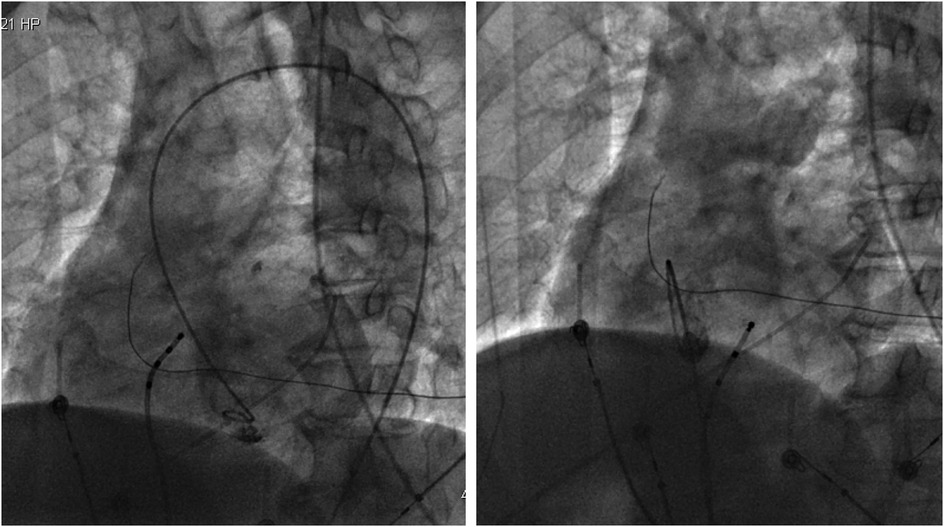

With the radiofrequency ablation power set at 30–40 W and the target temperature at 55 °C, the radiofrequency transmission lasted up to 90 s (Figure 2). During the ablation process, steam pop was not perceived, and there were no sudden changes in ablation parameters such as impedance、power or pressure values (Figure 2). After the termination of radiofrequency, the ventricular premature beats were significantly reduced. During the observation period after ablation (not immediately after), the patient suddenly complained of chest tightness, shortness of breath, and chest pain, and the blood pressure dropped to 102/65 mmHg (baseline blood pressure value: 149/78 mmHg). x-ray fluoroscopy observation showed a translucent shadow around the heart in the pericardial cavity (Figure 3), and the patient was suspected of having pericardial tamponade. Pericardial puncture and drainage were immediately performed. After slowly withdrawing 150 ml of bright red blood, no more blood was withdrawn, and the patient's blood pressure gradually recovered and tended to be stable. The ACT value immediately before pericardiocentesis was 126 s. Protamine was not administered and no additional heparin was administered due to the short duration of ablation. The unexpectedly low ACT at the time of pericardiocentesis may reflect partial heparin metabolism and consumption. Blood gas analysis of the red blood cells drawn from the pericardium suggested arterial blood. Under fluoroscopy, the translucent zone around the heart was smaller than before. In order to further clarify the perforation site, angiography was performed in the left and right ventricles(Supplementary Videos S1–S4), and it was found that the contrast agent did not extravasate outside the cardiac cavity (Figures 4A,B). Bedside transthoracic echocardiography showed that the pericardial effusion did not further increase. After indwelling the pericardial drainage tube, the patient was returned to the cardiac care unit for further observation. After 1 day of continuous drainage, no effusion was drained, and continuous review of echocardiography showed no obvious effusion (Supplementary Figures C,D). The patient was discharged after the drainage tube was removed.

Figure 4

(Left) Left ventricular angiography showing no contrast agent extravasation into the pericardial cavity. (Right) Right ventricular angiography showing no contrast agent extravasation into the pericardium.